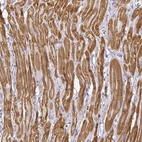

Immunohistochemistry analysis in human heart muscle and liver tissues using HPA005953 antibody. Corresponding MYOM2 RNA-seq data are presented for the same tissues.